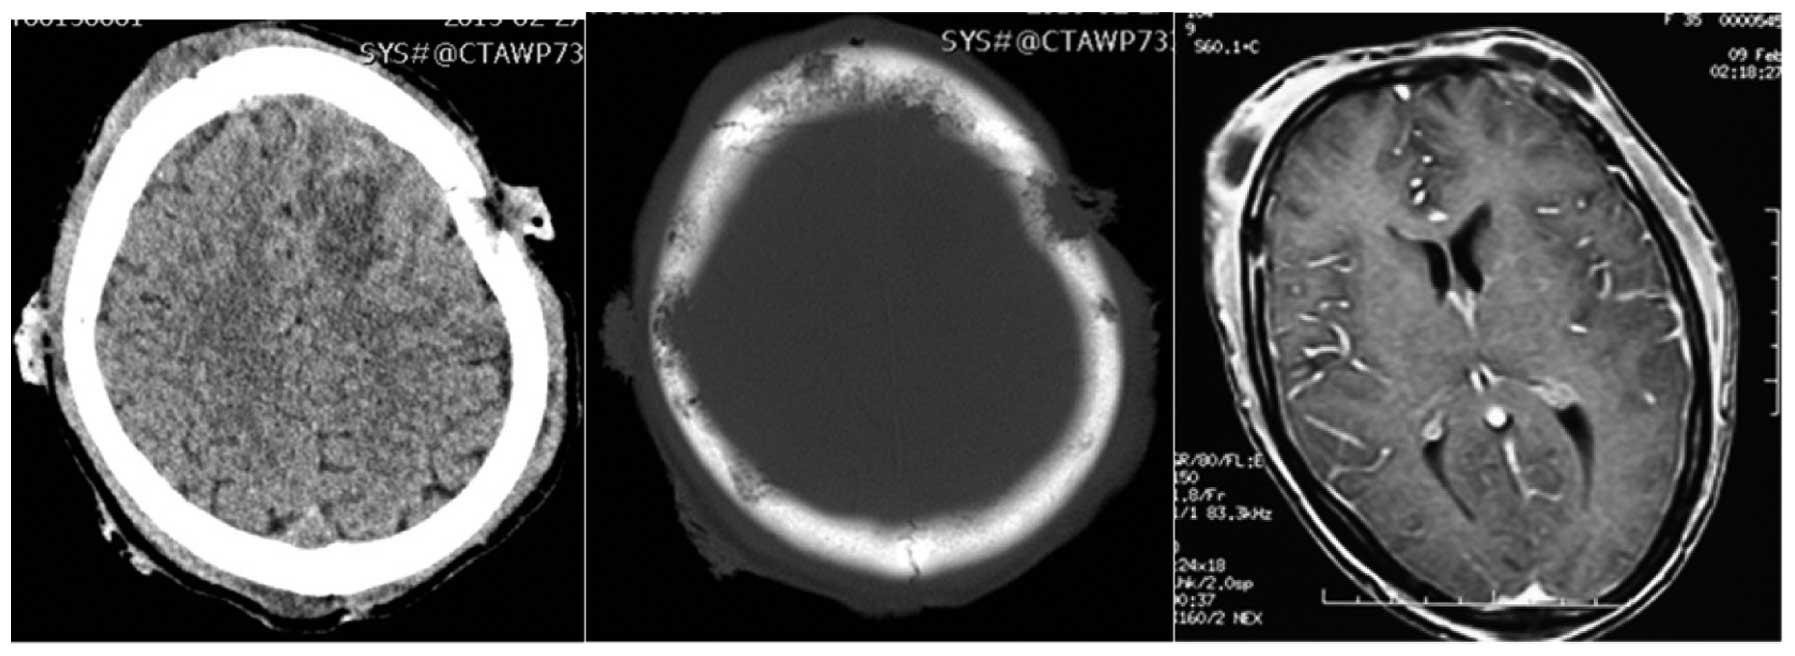

A 36-year-old female, a native of Hunan province in central China, had a 2 month history of subcutaneous abscess and a 1 month history of intermittent fever, cough and anhelation. The patient was informed that she had been infected with P. marneffei 1 year previously. Since then, the masses had gradually increased both in size and numbers. Despite the use of therapy with various antibacterial antibiotics for tuberculosis, the granulomatous lesions in the left upper lobe of the lungs persisted, the condition failed to improve and gradually deteriorated. For further treatment, the patient was admitted to The Second Xiangya Hospital of Central South University (Changsha, China) on February 25th 2015. Physical examination revealed a body temperature of 39.1°C, a pulse rate of 140 beats/min. Routine blood examination revealed the following: White blood cell count, 15.13×10−9/l (normal level, 3.5–9.5×109/l), red blood cell count, 3.39×1012/l (normal level, 4.3–5.8×1012/l) and hemoglobin level, 88 g/l (normal level, 130–175 g/l). Chest radiographs and chest computed tomography revealed multiple patchy exudative shadows, thick-walled hollow inner part of the visible lesions, bilateral pleural and pericardial effusion in the lungs (Fig. 1).

Figure 1.

Chest radiographs and computed tomography scans revealed multiple patchy exudative shadows and a thick-walled hollow inner part of the visible lesions in the lung.